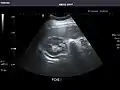

Liver

Liver: Diffusely homogeneous and normal in echogenicity. No focal mass or contour nodularity. No intrahepatic biliary ductal dilatation.

In patients with deranged liver function tests, ultrasound may show increased liver size (hepatomegaly), increased reflectiveness (which might, for example, indicate cholestasis), gallbladder or bile duct diseases, or a tumor in the liver.